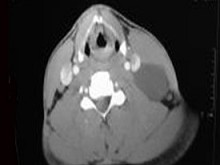

十產歲患者,女性,因頸前正中包塊3年入院,查體:頸前胸鎖乳突肌前緣上1/3外可觸及一圓形包塊,囊性,無壓痛,不隨吞咽上下活動。

6.CT檢查結果見下圖,本患者應考慮為  (    )

7.如果考慮為你所選的上述疾病,手術前應該完善下面那個檢查  (    )

正確答案:6.C;7.E